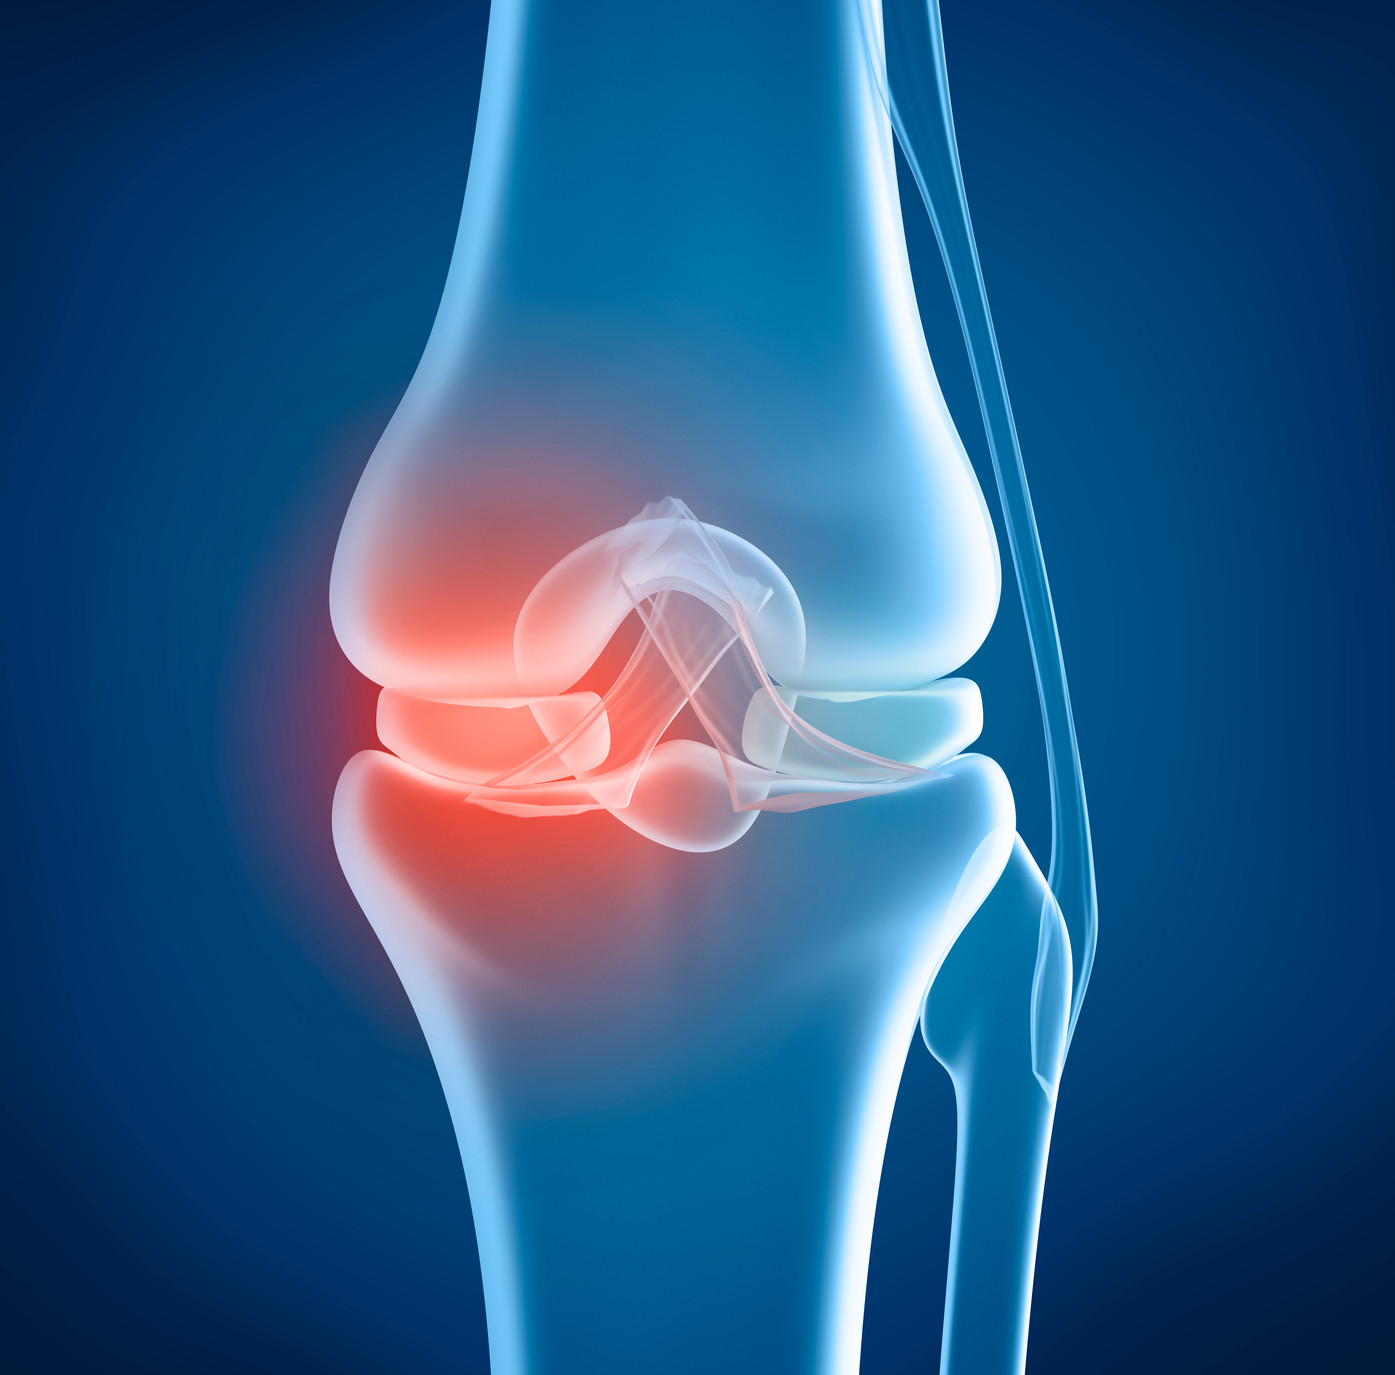

Knee Replacement

Advanced knee surgery.